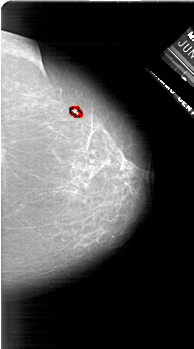

A_1624_1.RIGHT_CC

RIGHT_CC LINES 6271 PIXELS_PER_LINE 3481 BITS_PER_PIXEL 12 RESOLUTION 43.5 OVERLAY

FILE: A_1624_1.RIGHT_CC.OVERLAY

TOTAL_ABNORMALITIES 1

ABNORMALITY 1

LESION_TYPE MASS SHAPE LOBULATED MARGINS OBSCURED

ASSESSMENT 4

SUBTLETY 2

PATHOLOGY MALIGNANT

TOTAL_OUTLINES 1

BOUNDARY